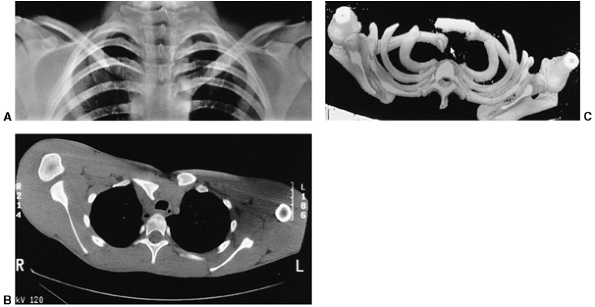

displacement can be anterior or posterior. Posterior displacement by

fracture or dislocation can cause dysphagia or respiratory compromise,

especially when the child’s head and neck are extended. Apical lordotic

radiographs are helpful, but computed tomography (CT) scans best

visualize the deformity (Fig. 33.10).

![]() |

|

Figure 33.10

Sternoclavicular separation. This 14-year-old boy sustained an injury to the right clavicle during a wrestling match when his shoulder was compressed against his chest wall. He complained of shortness of breath, especially when he extended his neck. A: The anteroposterior radiograph demonstrates asymmetry of the sternal position of the clavicle. B: The computed tomographic scan demonstrates posterior displacement of the medial end of the right clavicle, which is near the trachea (arrow). C: A three-dimensional reconstruction, with a cephalic projection, demonstrates the posterior and midline displacement of the clavicle. |